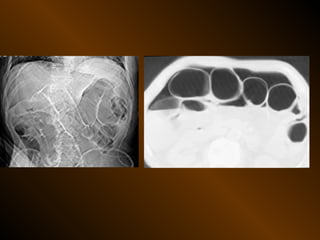

CĂNG GIÃN ỐNG TIÊU HÓA

PHÂN BIỆT

RUỘT NON – ĐẠI TRÀNG

• Các nếp Kerckring

• Nếp ngấn thanh mạc

• Khẩu kính

• Số lượng quai

• Phân bố các quai ruột

• Cao / rộng

• Chất cặn bã

PHÂN BIỆT RUỘT NON– ĐẠI TRÀNG • Các nếp Kerckring • Nếp ngấn thanh mạc • Khẩu kính • Số lượng quai • Phân bố các quai ruột • Cao / rộng • Chất cặn bã